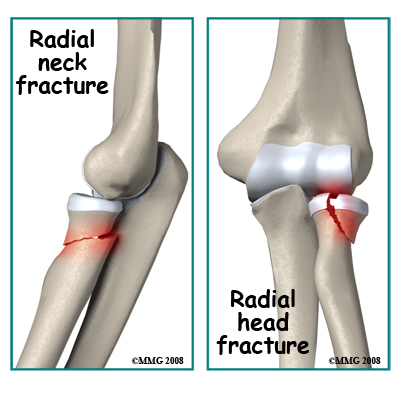

Fractures of the shaft of the radius are not discussed here. Fractures that directly affect the elbow joint are discussed below. Radial Neck Fractures: Longitudinal compression forces such as those resulting from a fall may cause a transverse fracture of the radial neck just below the head of the radius. A variable amount of compression and skewing of the bones can occur. A direct impact on the elbow may also cause this fracture. Due to the importance of the radial head in the functioning of the forearm, skewing of the bones as a result of this injury may limit forearm rotation. Also, due to the radial head being covered by articular cartilage a fracture through the neck region may deprive the radial head of its blood supply.

Radial Neck Fractures: Longitudinal compression forces such as those resulting from a fall may cause a transverse fracture of the radial neck just below the head of the radius. A variable amount of compression and skewing of the bones can occur. A direct impact on the elbow may also cause this fracture. Due to the importance of the radial head in the functioning of the forearm, skewing of the bones as a result of this injury may limit forearm rotation. Also, due to the radial head being covered by articular cartilage a fracture through the neck region may deprive the radial head of its blood supply.

Radial Head Fractures. Axial forces compressing the radial head against the capitellum cause these injuries. This may happen with a fall, especially with the elbow slightly bent. The result is a fracture with a depressed segment of the radial head. The broken segment is most likely deprived of its blood supply. Treatment depends on the extent of the injury and the degree of displacement and angulation. The more severely displaced fractures may be treated by surgery.

Radial Head and Neck Fractures. Many of these fractures do not need surgery. However, where the broken segment of the radial head is large or the amount of angulation or displacement is significant it is better to do an ORIF operation. As the bone fragments of this fracture are small and have usually lost their blood supply, this is a challenging operation. The results from surgery to repair the fracture may not be that good. It used to be popular to remove the radial head completely when it was badly injured however this operation has been shown to affect the functioning of the forearm and wrist, so many surgeons attempt to preserve the radial head or in some situations replace it with a prosthetic head. In the case of radial neck fractures, the blood supply of the fragments may be intact. In these cases, closed reduction to restore the position may be a good solution, as the bone will heal. Unfortunately, any residual angulation at the neck may cause problems with rotation of the forearm.